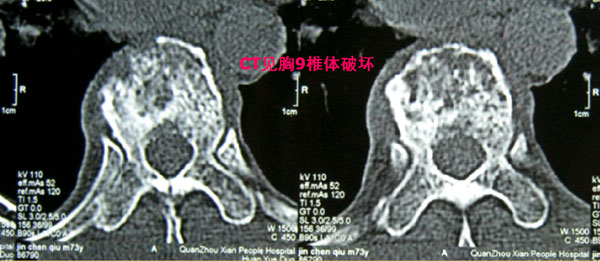

该男性患者现年73岁,自述其反复胸背部疼痛约8个多月,病情加重1周后入院。瑞康医院骨脊柱科专家为其检查身体发现,其胸背部有压痛、叩击痛。患者的胸椎X光片显示其胸9椎体有病理性压缩骨折(图1),胸椎CT片显示其椎体破坏(图2),胸椎MRI检查显示其胸9椎体及椎弓呈现长T1异常信号改变(即肿瘤样改变),椎体后缘突入椎管,导致脊髓受压,增强MRI可见病灶强化影(图3)。前列腺MRI提示该患者患前列腺癌的可能性较大。

胸9椎体破坏